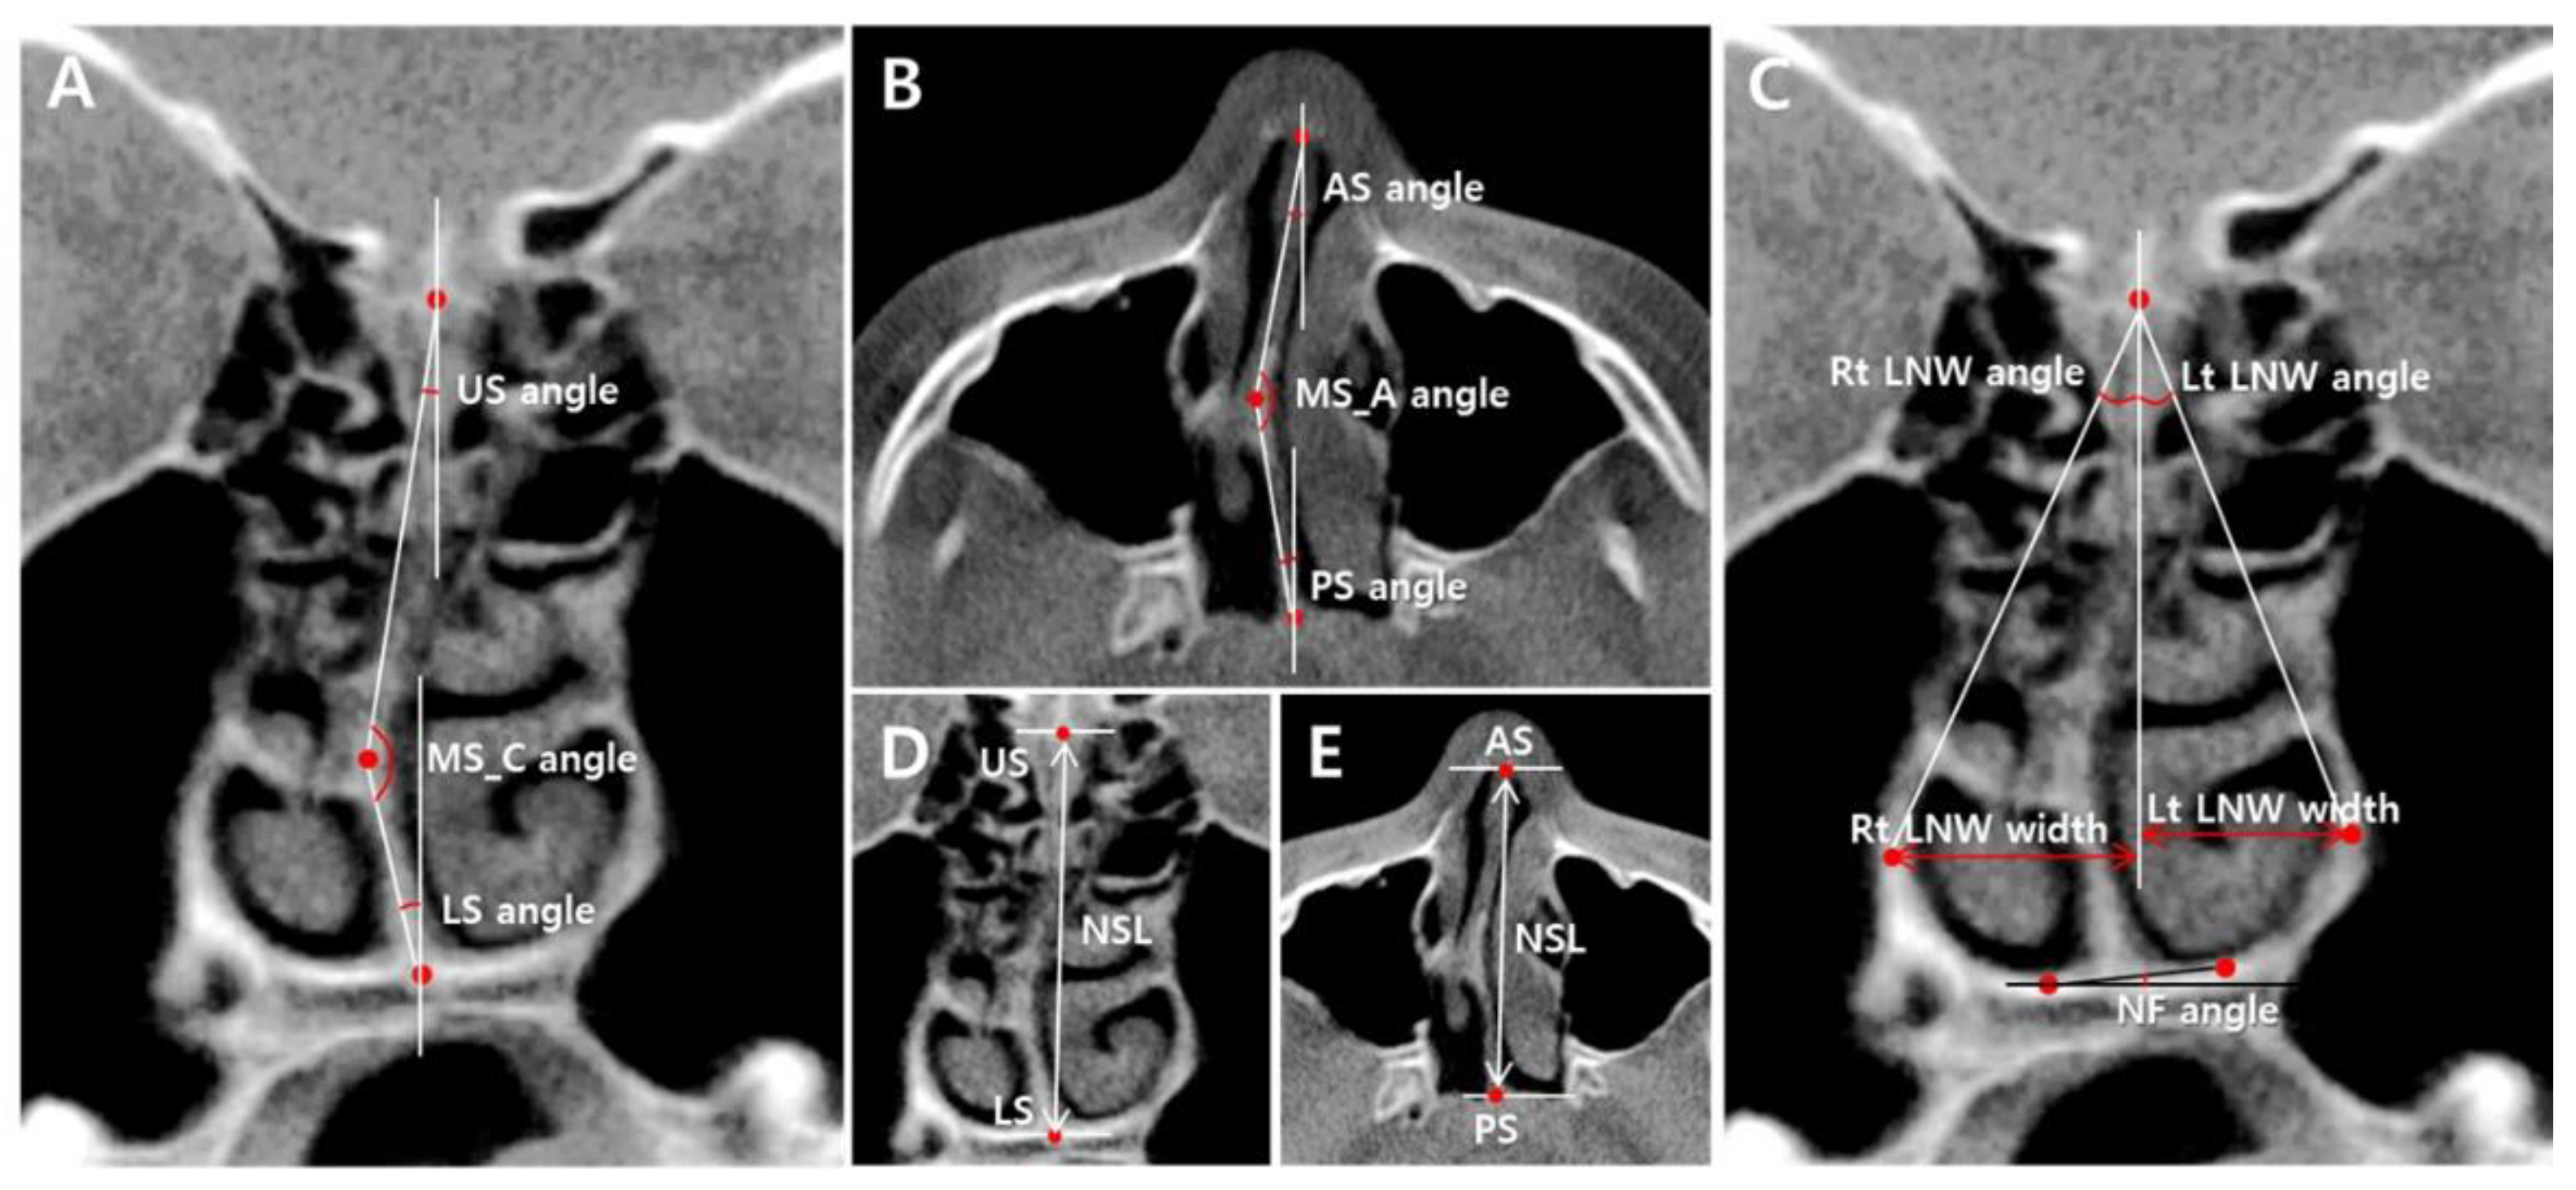

From www.mdpi.com

Applied Sciences Free FullText A CBCT Evaluation of Nasal Septal What Is A Nasal Spur A deviated septum happens when the nasal septum is out of position to one side, making one nasal air passage smaller than the. In addition, healthcare providers may recommend. It is a short bend either happening in the cartilaginous portion or in the bony portion of the nasal. A septoplasty is a surgery for treating nasal blockage. A nasal septal. What Is A Nasal Spur.